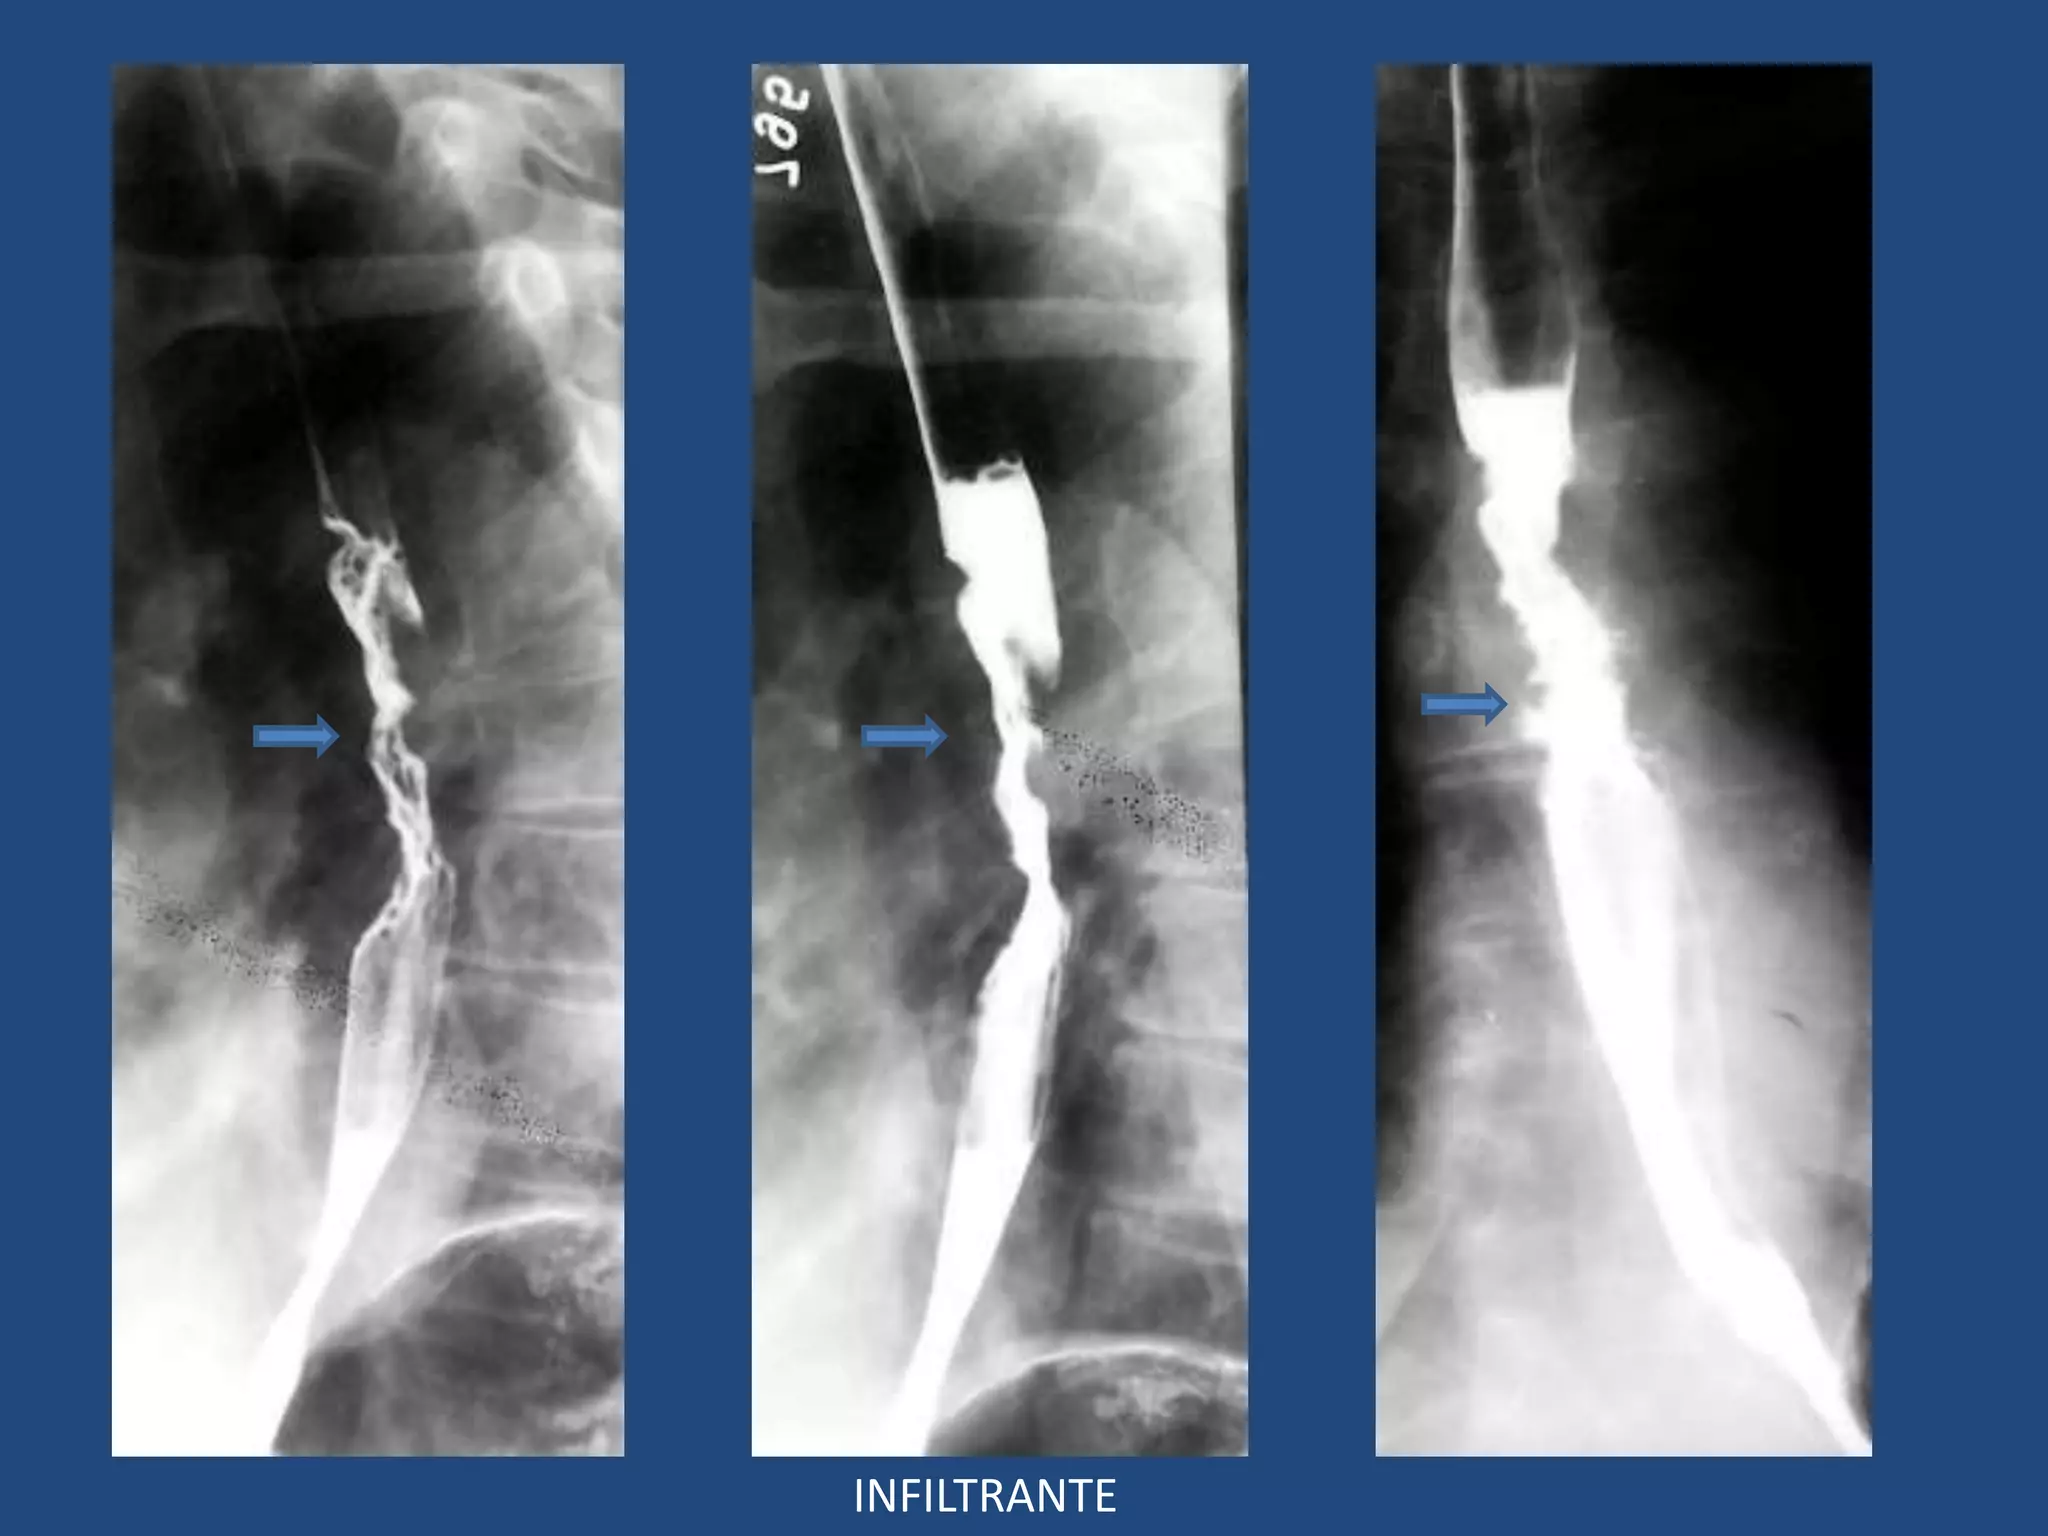

ESÓFAGO: TUMORES MALIGNOS

• Hallazgos Avanzados:

3 Patrones típicos simples o combinados:

- Polipoide

- Infiltrante

- Ulcerado

POLIPOIDEA

INFILTRANTE

ULCERADO

Ulceración

Infiltrativo

MIXTO